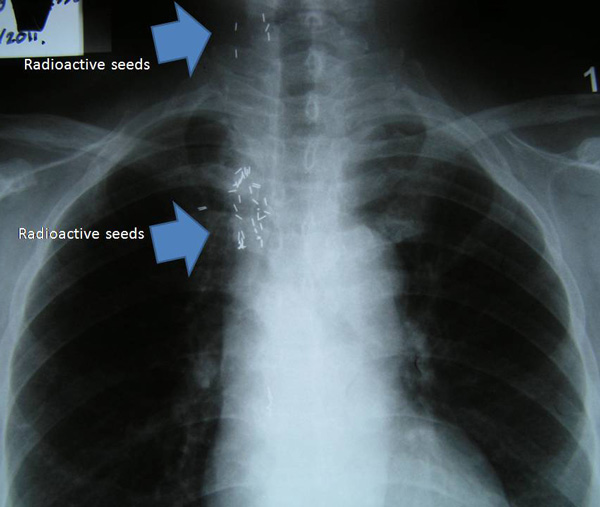

The doctor in Kuching suggested chemotherapy. She refused. The family decided to bring her to China for medical treatment. She received treatments such as chemotherapy, cryoablation and radioactive seeding  in the Chinese hospital.

She stayed about one to two weeks in China during each trip there.  She returned home feeling “alright” only to go back to China again for more treatment each year.